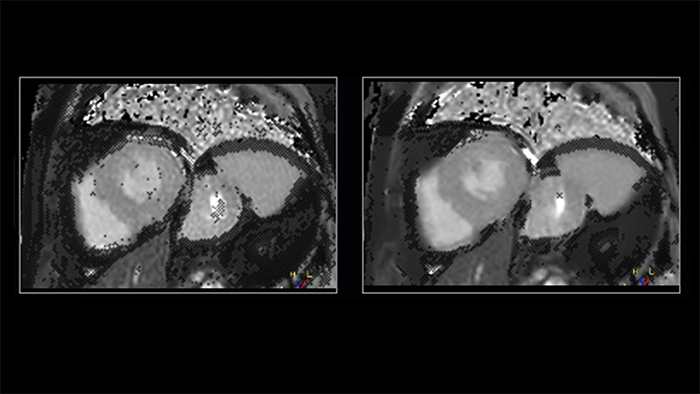

Shorter readouts lead to improved diagnostic confidence

Shorter data readouts [2] enabled by Compressed SENSE provide benefit for black bloods and T1 mapping as well with sharper images acquired. For T1 mapping this results in fewer unconfident pixels on the resulting T1 map (see Fig. 3).

Figure 3. T1 mapping: shorter readouts using C-SENSE x3 leads to fewer unconfident pixels. Left to right: SENSE x2, C-SENSE x3